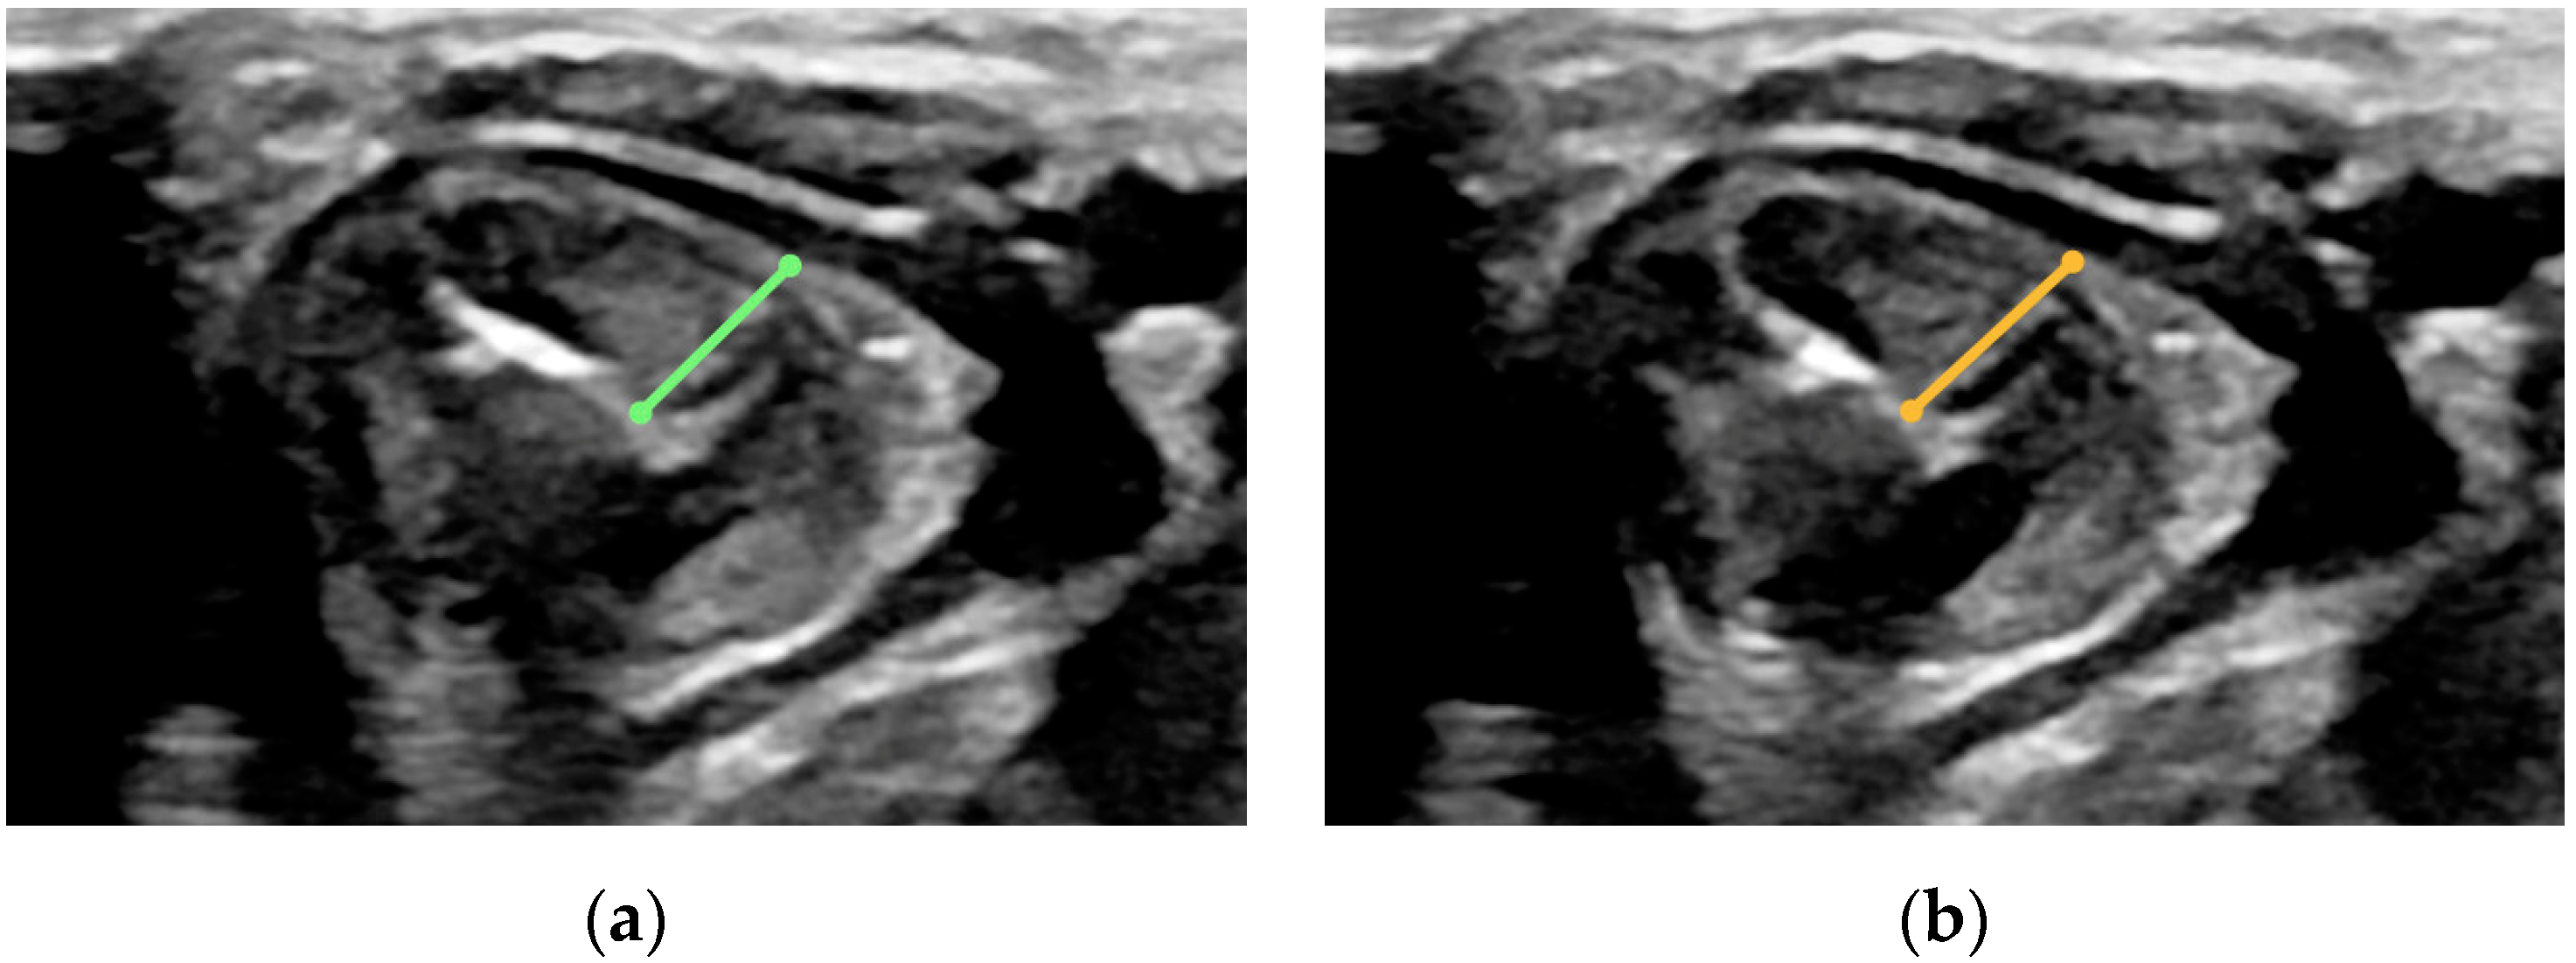

- Angle formed by the vocal cords during calm breathing, considering the opening angle of individual chords (measurement taken in the transverse plane with a line drawn from posterior part of the anterior commissure to the medial margins of the arytenoid gland) (Figure A6);